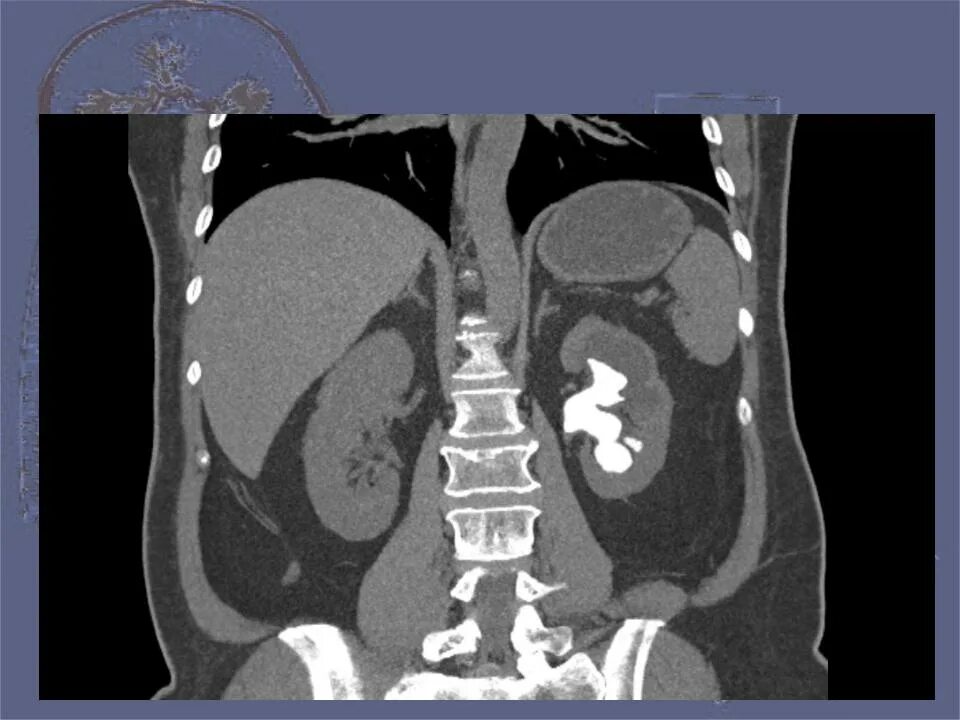

Гидронефроз 1 степени